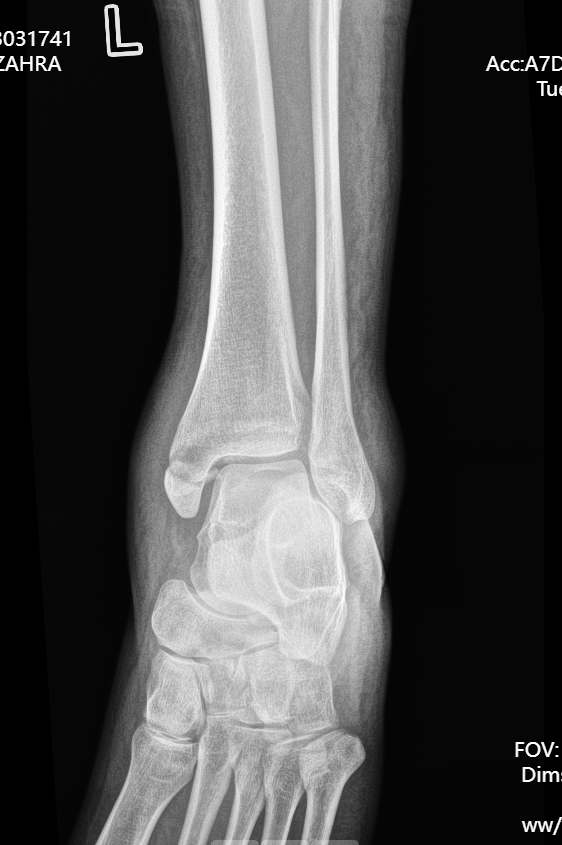

患者因意外受伤后踝关节疼痛、肿胀、无法行走,急诊就诊于我院。

经检查确诊为旋前外旋 Ⅳ 度踝关节骨折,包含腓骨中段骨折、内踝骨折、后踝骨折及下胫腓联合分离,属于临床中结构复杂、稳定性破坏较严重的踝关节损伤。